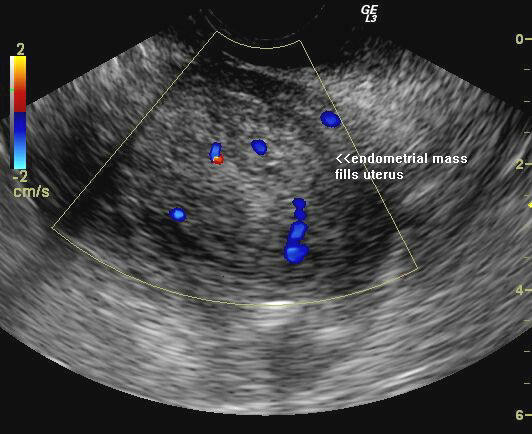

Ultrasound images of malignant polyp of uterus.

The above ultrasound images show 1) apparently marked thickening of the endometrium (19mm.) on             transabdominal sonography. 2) on transvaginal imaging, there is a large polyp like mass (14 x 22 mm.) occupying the uterine cavity. 3) color doppler imaging shows feeding vessels supplying the polyp. Histopathology confirmed endometrial carcinoma (adneocarcinoma).Images by Joe Antony, MD, Cochin, India.